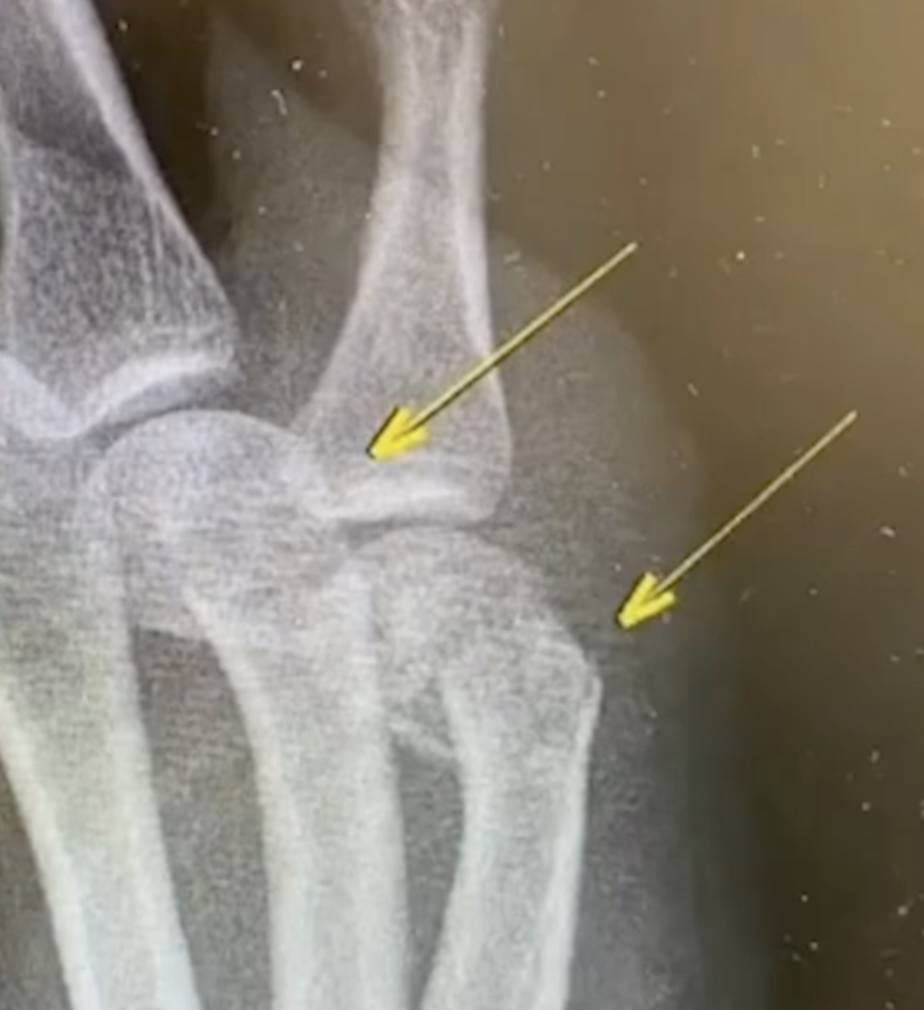

该患者右手第四第五掌骨肿胀明显

没想到把自己捶骨折了